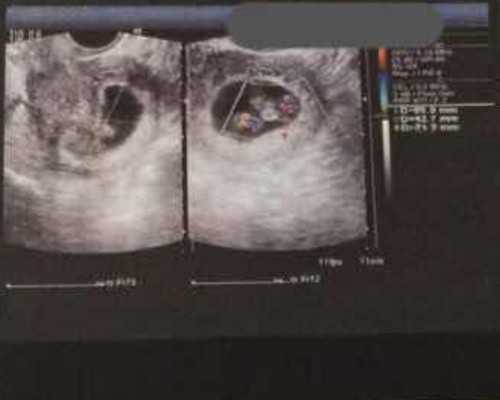

目前在长沙做第三代试管婴儿的价格在10万左右,但是没有包生男孩的服务。第三代试管婴儿技术也叫胚胎植入前基因诊断技术,虽然在技术上可以选择胎儿的性别,但国家法律明确禁止非医学用途的性别鉴定,正常情况下,只有染色体上携带一些遗传病的患者才能通过性别选择避免遗传病,从而生下健康的宝宝。因此,在长沙,无论是在公立医院还是医疗机构,只要是正规医院都没有包生男孩的服务,也没办法包成功,所以不要被好听的口号所迷惑。在长沙公立医院做三代试管生男孩女孩的概率各占50%,也就是说,生男孩还是女孩取决于个人运气。

4、PGD/PGS筛查、检测(20000~40000元)

PGD/PGS筛选是第三代试管婴儿技术的特殊优势,可以为胚胎做好工作PGS/PGD的囊胚基因、染色体筛选、诊断出274种不良遗传基因和染色体异常。经检查筛选后,医生会选择最健康的、优质胚胎移植到女性宫腔,经过这一系列检查,胚胎着床率会大大提高,这就是为什么第三代试管婴儿很贵的原因。